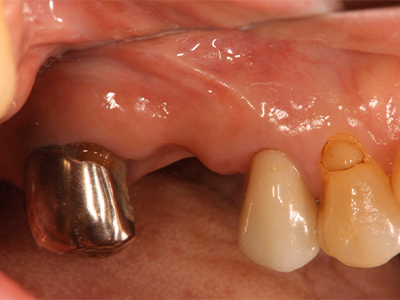

インプラント治療

インプラント1歯欠損(臼歯・症例)

治療前後写真

治療前

治療後

年齢・性別

80歳・男性

来院理由

右下の歯がぐらぐらして咬めない

治療内容

- ① 重度歯周病のため抜歯 → 治癒後プランニング

- ② 1次手術時に骨造成を併用してインプラント埋入

- ③ 3ヶ月後、2次手術時に歯肉移植(歯肉補強術)を併用

- ④ 最終補綴装着後、メンテナンスへ移行

治療期間

約5ヶ月

費用

450,000円

リスク・副作用

清掃・メンテナンス不良でインプラント周囲炎・感染・脱落の可能性/術後の痛み・腫脹・出血

医院コメント

骨造成と歯肉補強を段階的に行い、清掃性・耐久性の高い周囲組織を再建。

埋入から15年経過時点でも良好に機能。